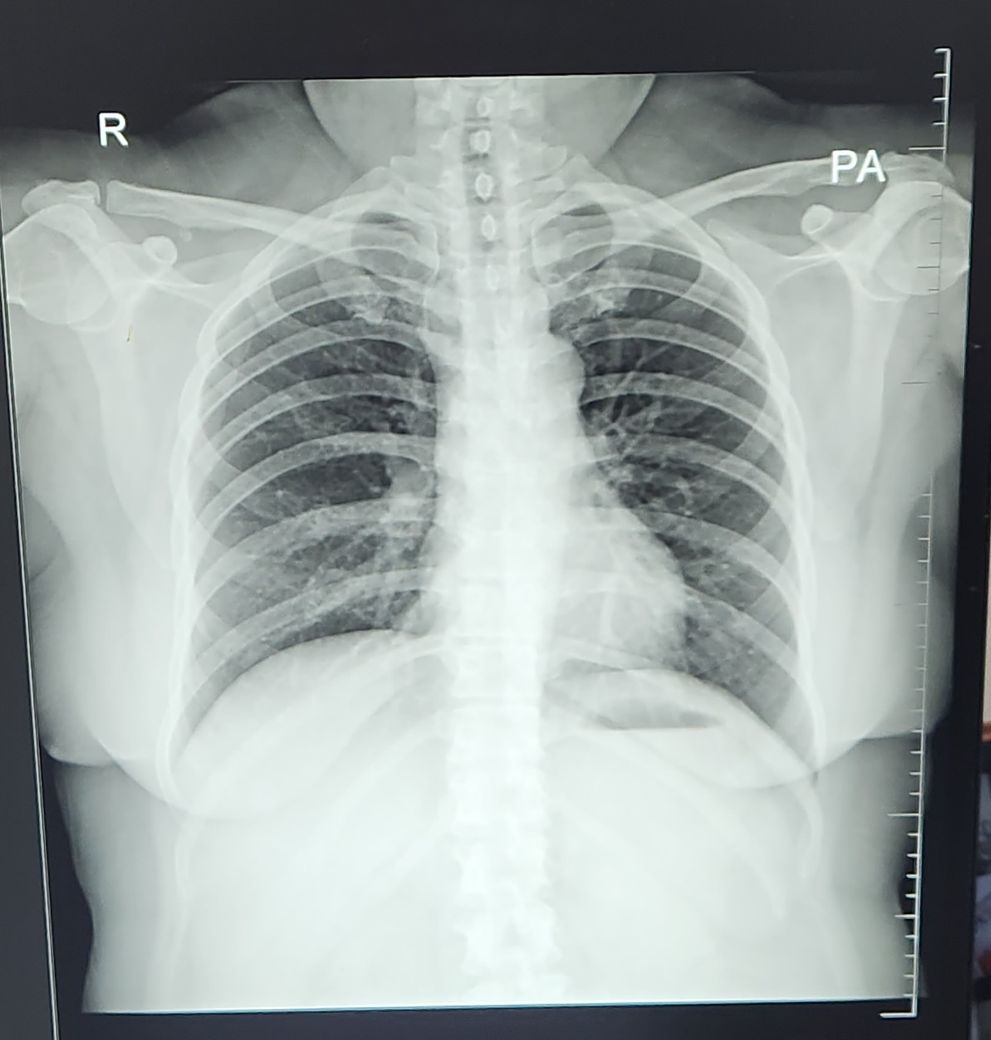

엑스레이좀 봐주세요. 기관지염이 맞나요?

항생제 20일복용, 각종 기침과 기관지염, 스테로이드, 소염진통제, 천식 약등을 복용해도 아예 호전이 없습니다. 엑스레이 사진상 기관지염이 맞나요?

대학병원 호흡기내과 에서는 기관지염이 아니라고 하는데 누가 맞는건지 모르겠습니다ㅜ

기관지염은 흉부 엑스레이에서 진단하기는 어렵답니다. 제가 봤을 때도 기관지염이 심하다고 느껴지지는 않아요. 아데노 감염이후라면 후비루 증후군일겁니다. 기침이 심하고 오래가는 것이 특징입니다. 콧물, 기침약을 드시면서 기다리다보면 좋아질 겁니다. 항생제는 그만 드셔도 될 것 같구요.